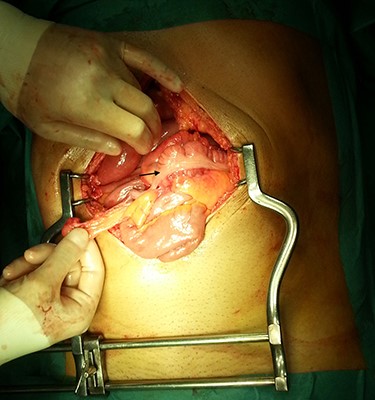

In the presence of an intestinal obstruction of an unclear cause, an exploratory laparotomy was proposed. A peritoneal encapsulation (Fig. 4) of the small bowel was identified, without intestinal ischemia. The peritoneal sac was located in the right abdominal quadrants, only partially involving the small bowel, so in the left quadrants there was normal caliber ileum externally to it. The membrane was excised and the peritoneal cavity was explored, showing signs of intestinal malrotation with medialization of the right colon (Fig. 5) and a retrocecal position of the terminal ileum leading to intestinal obstruction (Fig. 6). After lysis of adhesions from the bowel to the membrane, the terminal ileum was released and complementary appendectomy was done. Histopathology revealed normal peritoneal tissue. After prolonged ileus, patient was discharged on the 8th postoperative day and presented asymptomatic 1 year later.

After excision of the accessory peritoneal membrane, signs of intestinal malrotation with medialization of the right colon were noted (arrow).